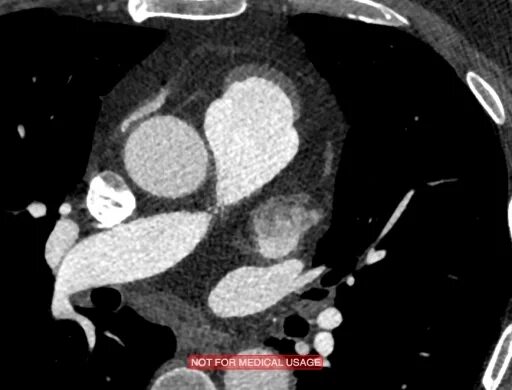

Тромбоз предсердий